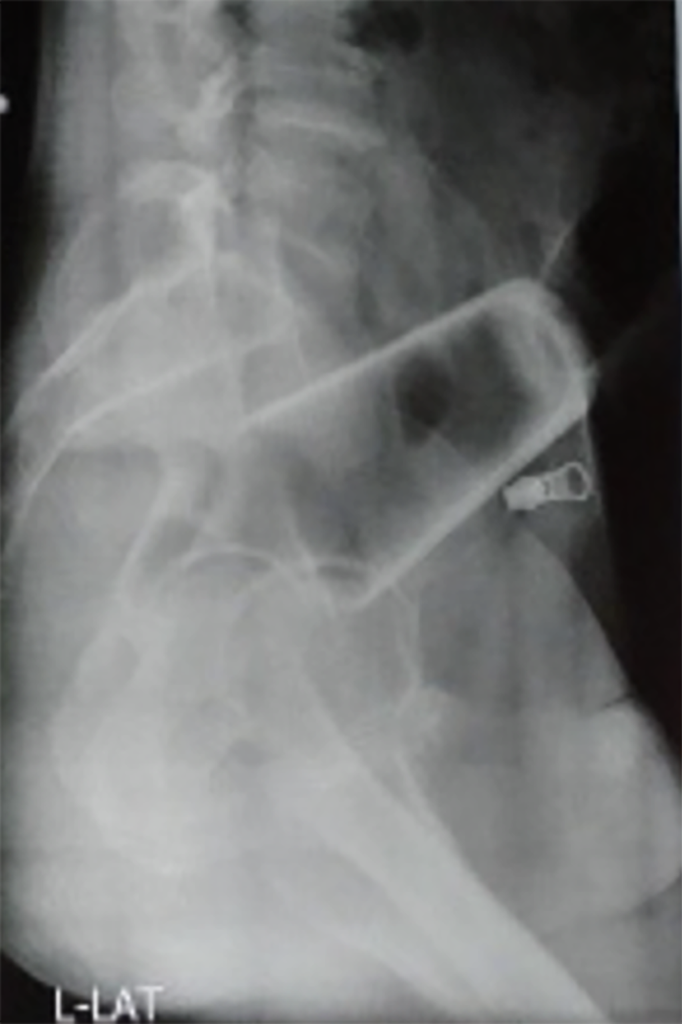

Bărbatul a spus că a încercat să scoată singur sticla, dar nu a reușit. După ce i-au făcut o radiografie, medicii au încercat să îndepărteze paharul fără operație, dar nu au reușit să-l extragă, deoarece era inversat.

Personalul medical a efectuat apoi o laparotomie exploratorie, care este o intervenție chirurgicală de deschidere a abdomenului.

Intervenția medicală extrem de neobișnuită a ajuns în Journal of Nepal Medical Association. „S-a încercat absorbirea paharului prin anus, dar acest lucru nu a reușit, deoarece paharul era sus, răsturnat și strâns încastrat”, au explicat medicii.

A fost nevoie de o intervenție și mai complicată: „De aceea s-a făcut enterostomia sigmoidă și s-a extras paharul de sticlă”.

O enterostomie este incizia chirurgicală într-un intestin, care au permis medicilor accesul direct la obiectul de sticlă.